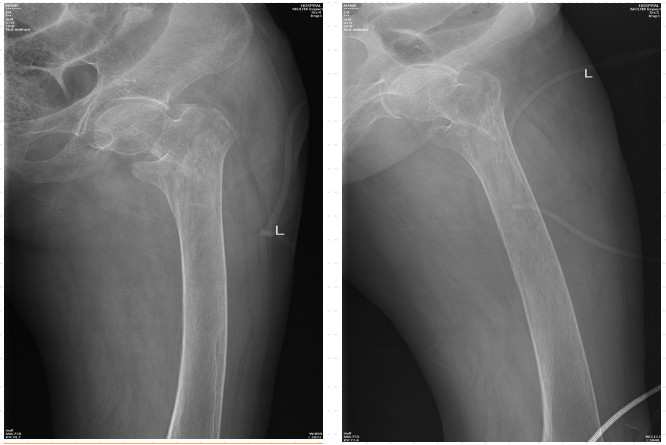

近日,88岁高龄的陈奶奶因滑倒摔伤,臀部着地,当即感到左髋部疼痛,无法站立行走,活动明显受限。陈奶奶的家人发现后立即将她送至黄播 急诊科进行救治。拍片后提示为左股骨粗隆间骨折,需要手术治疗。

在询问陈奶奶的家属后得知,陈奶奶年事已高,疾病缠身,除了有冠心病、心房颤动、全心衰等心脏方面的问题,同时合并有老年性骨质疏松、主动脉硬化、甲状腺功能亢进(未进行治疗)、贫血、凝血功能异常等基础疾病。另外,陈奶奶曾于2020年在黄播 顺利完成了“右侧股骨粗隆间骨折闭合复位APFN内固定术”,术后恢复良好,3年来生活基本恢复正常。

不幸的是,这次受伤造成了左股骨粗隆间骨折,陈奶奶将迎来第二次的髋关节手术!此次手术的风险比上一次更高,术后治疗与康复也更具有挑战性!